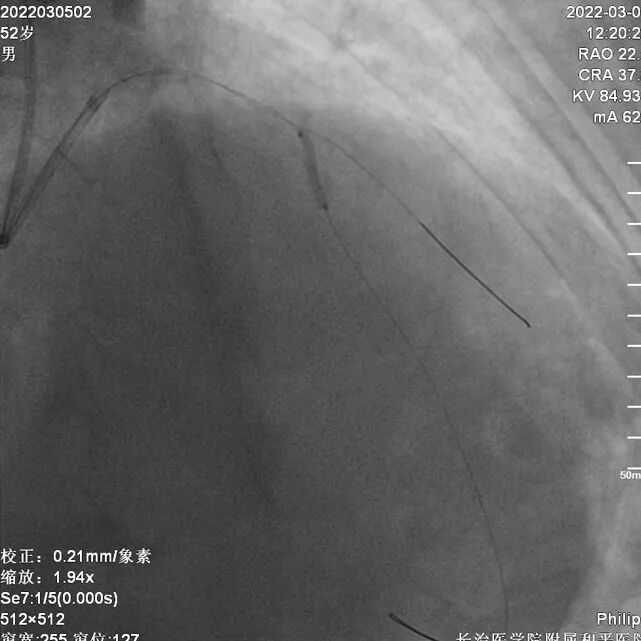

CAG

干预右冠

6FEBU3.5Guiding、Runthrough导丝、Sion导丝、2.0x15mm球囊

2.5x10mm切割球囊